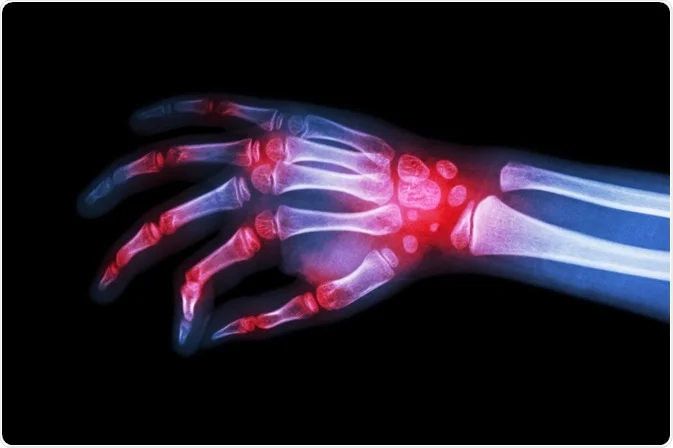

Rheumatology is a branch of medicine that focuses on the diagnosis and treatment of rheumatic diseases, which are characterized by inflammation and pain in the muscles, joints, and connective tissues. Rheumatologists are specialists who manage these conditions, which can be both autoimmune and inflammatory in nature. An autoimmune disorder where the immune system attacks the synovium (lining of the joints). A systemic autoimmune disease affecting multiple organs, including the skin, joints, kidneys, and brain. An inflammatory disease primarily affecting the spine, leading to fusion of the vertebrae. Chronic back pain, stiffness, reduced flexibility, and, in severe cases, a forward-stooped posture. A group of diseases involving hardening and tightening of the skin and connective tissues. Immunosuppressants, corticosteroids, medications for specific symptoms. Thickened skin, Raynaud's phenomenon, digestive issues, organ involvement. Blood tests for inflammatory markers (CRP, ESR), autoantibodies (RF, ANA), and other specific markers.